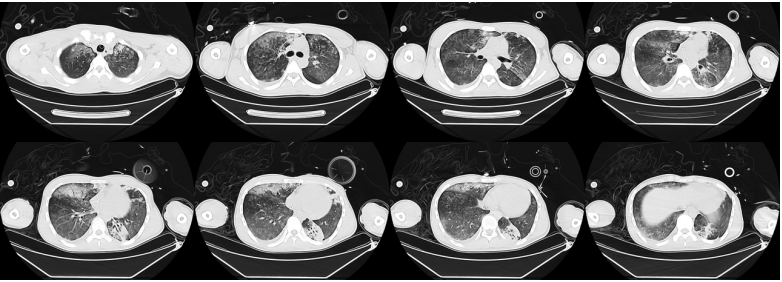

对于重症腺病毒肺炎,激素的使用需要慎重。对于肺内肺外表现及炎症反应都非常严重的患者,激素可能有助于改善病情。2013年由全军传染病专业委员会发表的《腺病毒感染诊疗指南》推荐,成人激素使用剂量相当于甲泼尼龙80~320 mg/d,具体可根据患者病情及个体差异调整。

对于抗腺病毒药物,尽管西多福韦目前是临床推荐用药,但并没有很强的证据,还需要通过临床应用来监测患者的病毒载量等。几种抗病毒药物(包括西多福韦、利巴韦林和更昔洛韦)已经显示出体内和体外抗腺病毒疗效。西多福韦是一种核苷酸类似物,在体外和体内均显示出抗病毒活性。主要用于严重腺病毒感染和免疫功能低下的患者,包括儿童、干细胞和实体器官移植患者。在免疫功能正常的患者中,西多福韦治疗腺病毒感染的疗效尚不明确。然而,在免疫功能正常的军事学员的几项临床试验中,西多福韦显示出临床获益和氧合的改善。未来仍有待于进一步验证其临床疗效。

图片